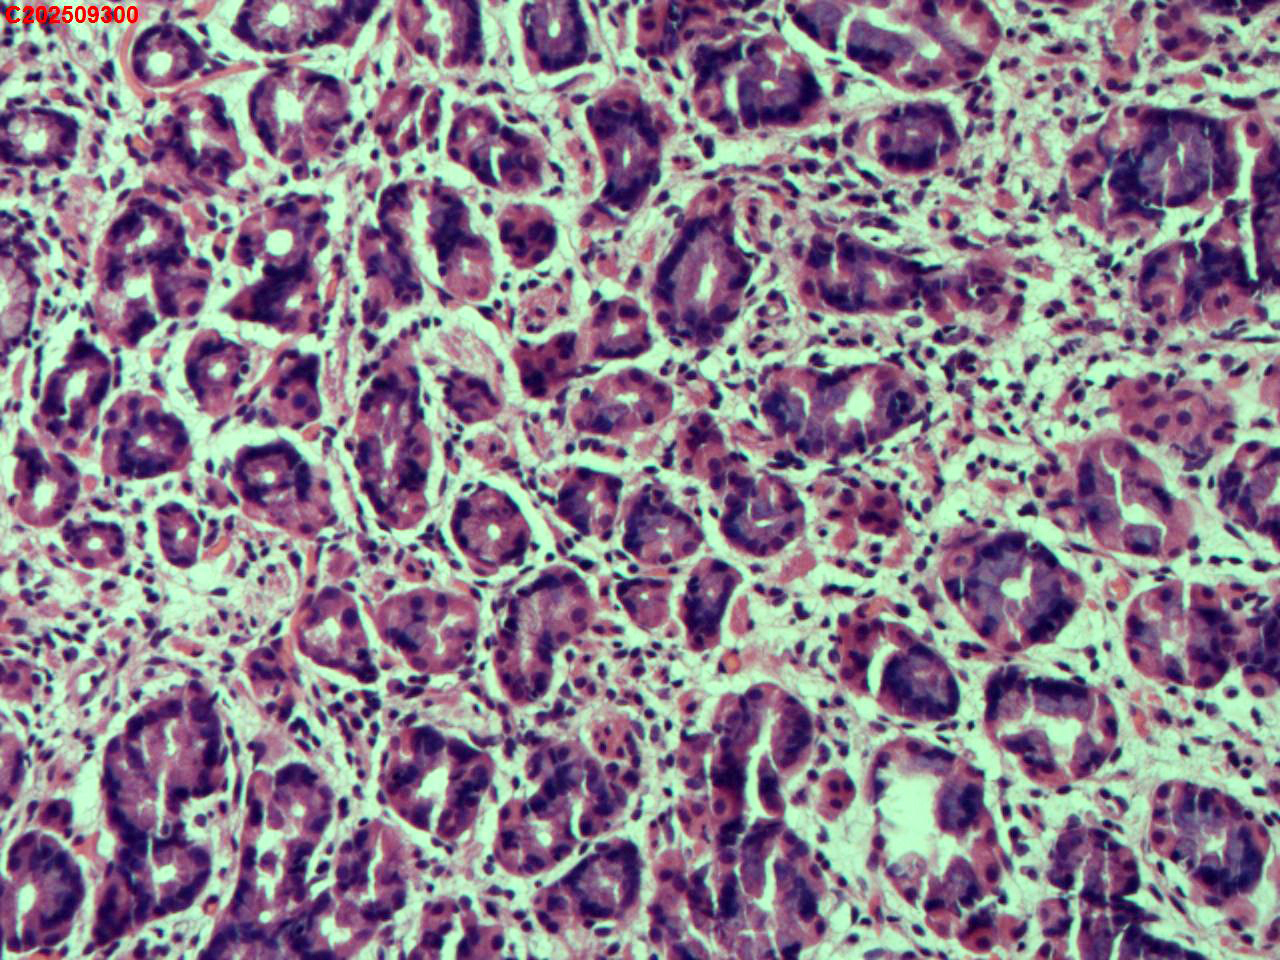

胃底粘膜

性别

女

年龄

44岁

临床诊断

胃息肉

一般病史

体检

标本名称

大体所见

胃底:可见一枚直径约2mm的半球形息肉。

增生性息肉